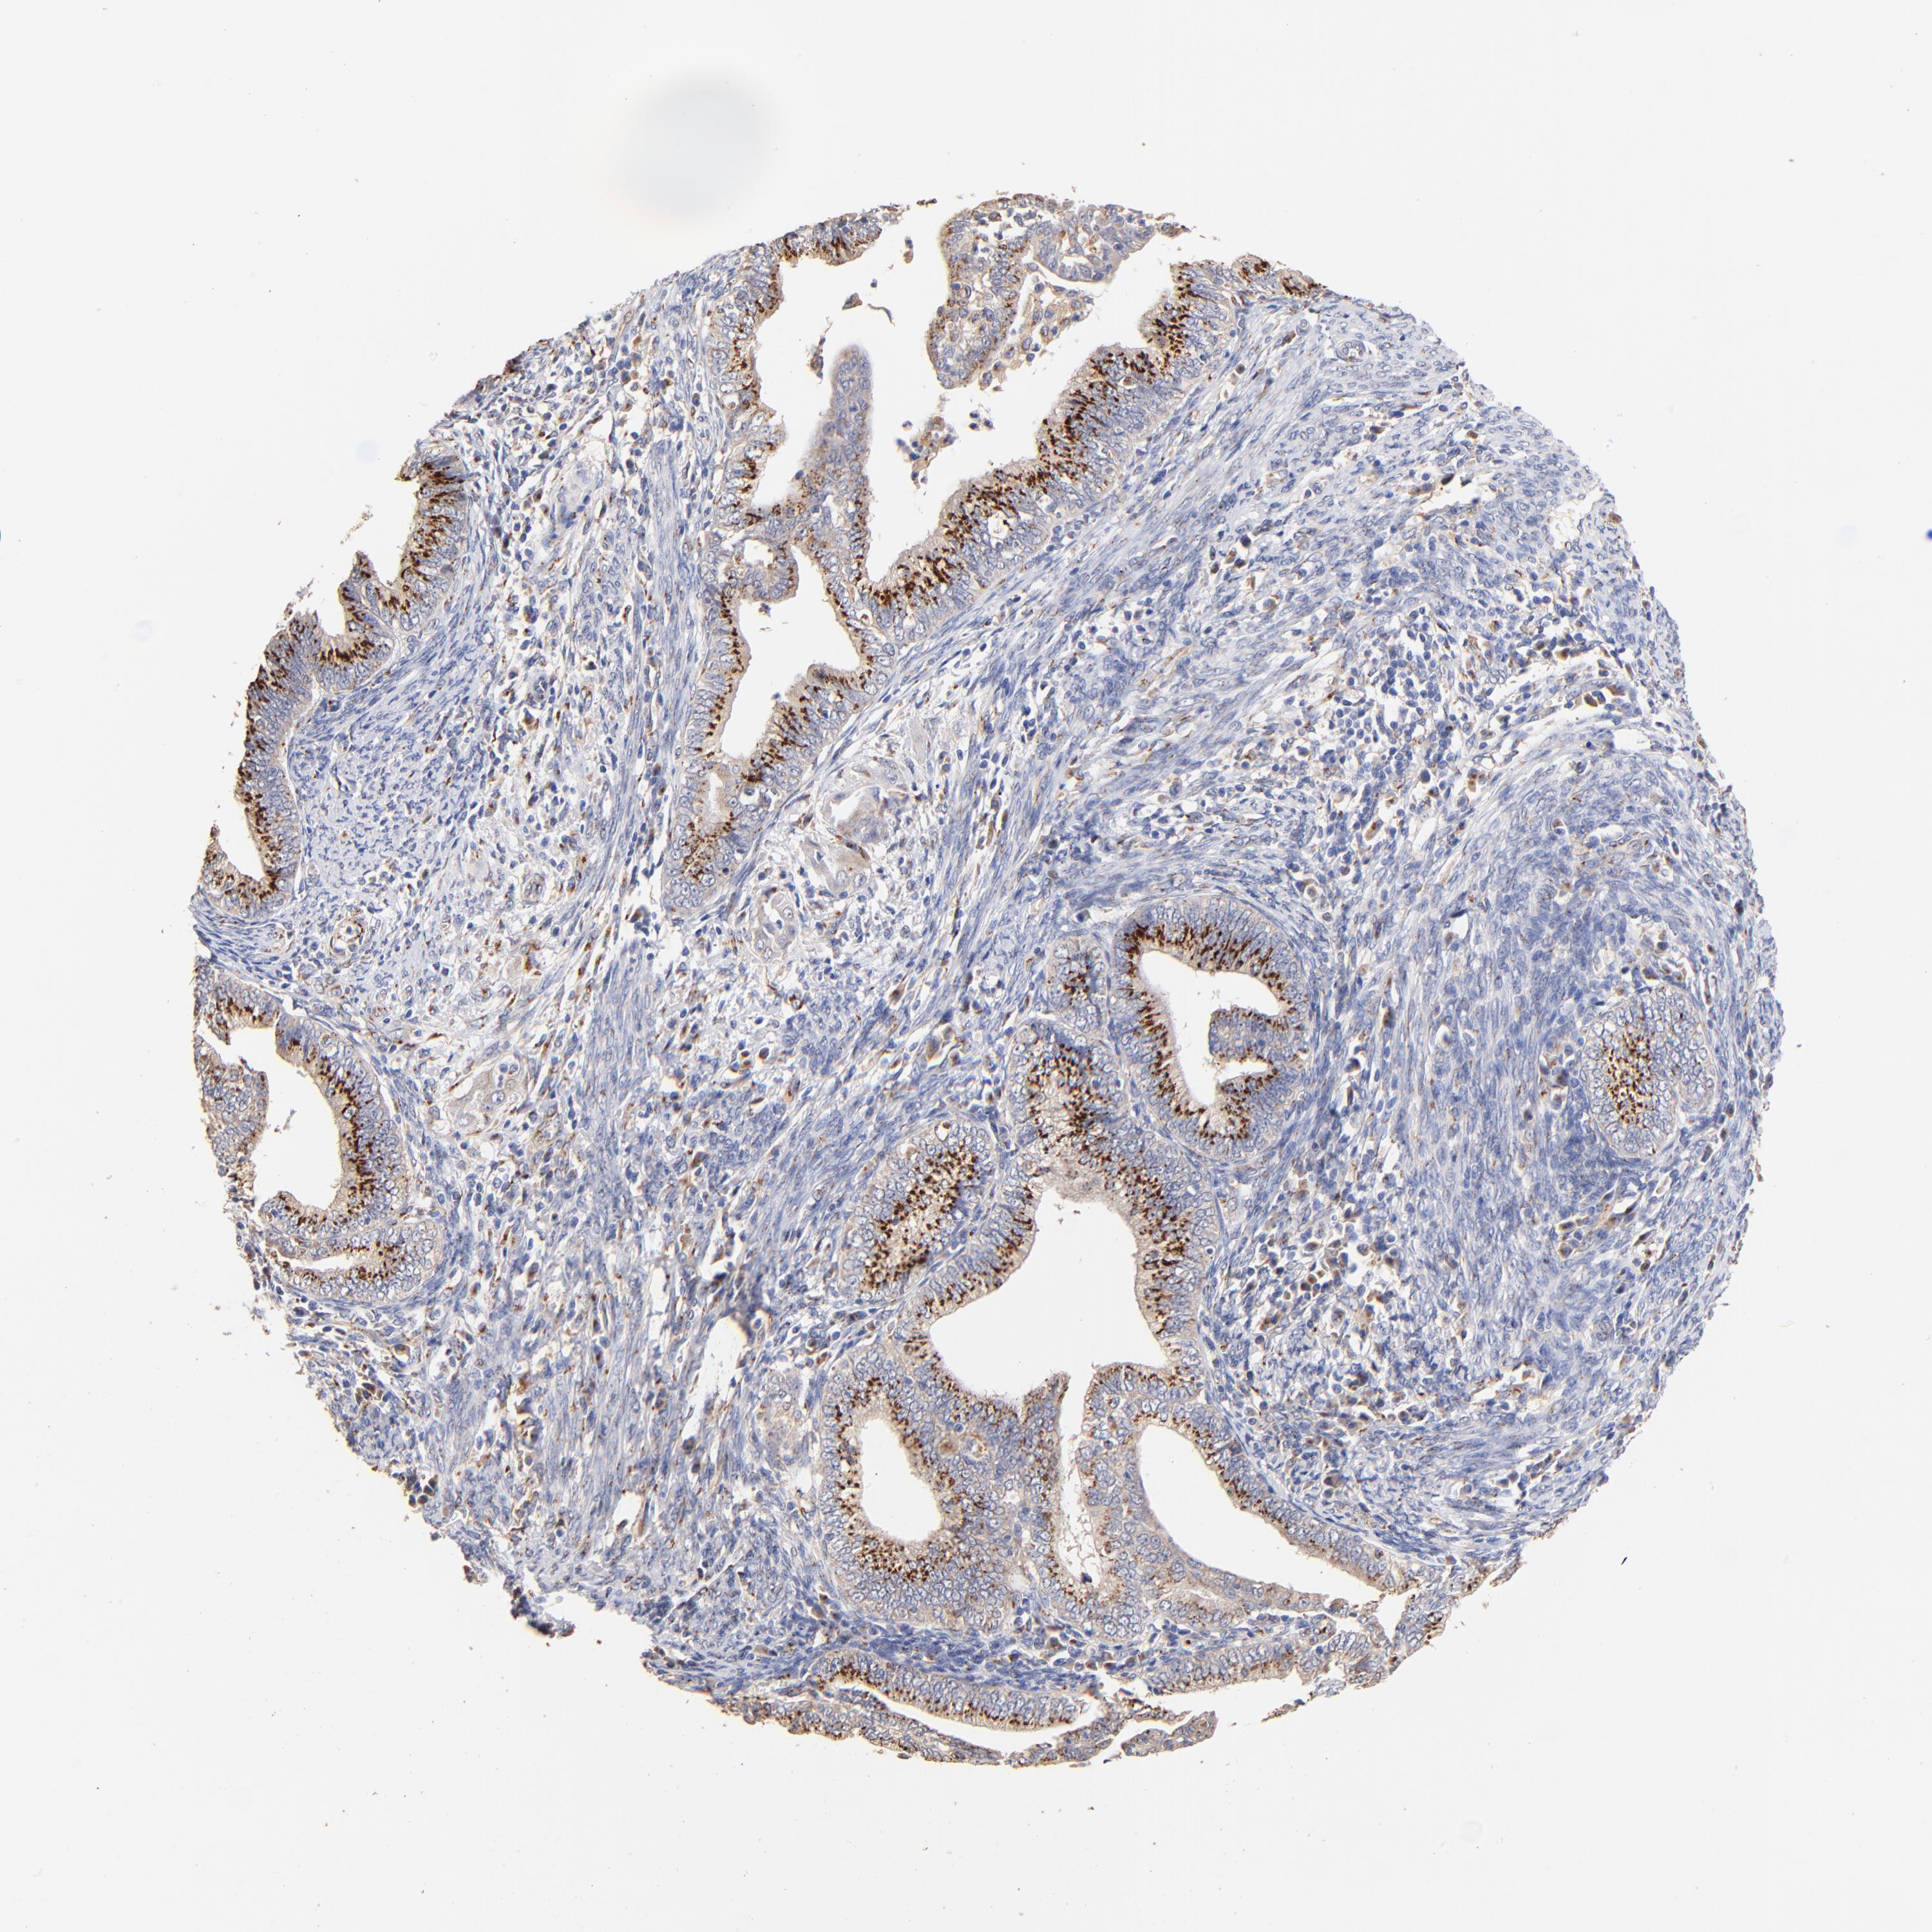

ENDOMETRIAL CANCER - Protein expressioni

A mouse-over function shows sample information and annotation data. Click on an image to view it in a full screen mode. Samples can be filtered based on level of antibody staining by selecting one or several of the following categories: high, medium, low and not detected. The assay and annotation is described here.

Note that samples used for immunohistochemistry by the Human Protein Atlas do not correspond to samples in the TCGA dataset.

Antibody stainingi

Antibody staining in the annotated cell types in the current human tissue is reported as not detected, low, medium, or high, based on conventional immunohistochemistry profiling in selected tissues. This score is based on the combination of the staining intensity and fraction of stained cells.

Each image is clickable and will lead to virtual microscopy that enables deeper exploration of all samples and also displays staining intensity scores, fraction scores and subcellular localization as well as patient and tissue information for each sample.

Antibody HPA023201

Staining

High

Medium

Low

Not detected

Intensity

Strong

Moderate

Weak

Negative

Quantity

>75%

75%-25%

<25%

None

Location

Nuclear

Cytoplasmic/membranous

Cytoplasmic/membranous,nuclear

Adenocarcinoma, NOS